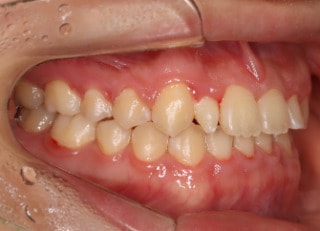

解説:下顎前突上顎劣勢長傾向で、上顎両側2番が矮小歯、右下2番先天欠如症例なので、上下前歯の幅径の比率を調節する必要があるケースです。(ご本人のご都合で治療中に来院できない期間がありました)

治療前